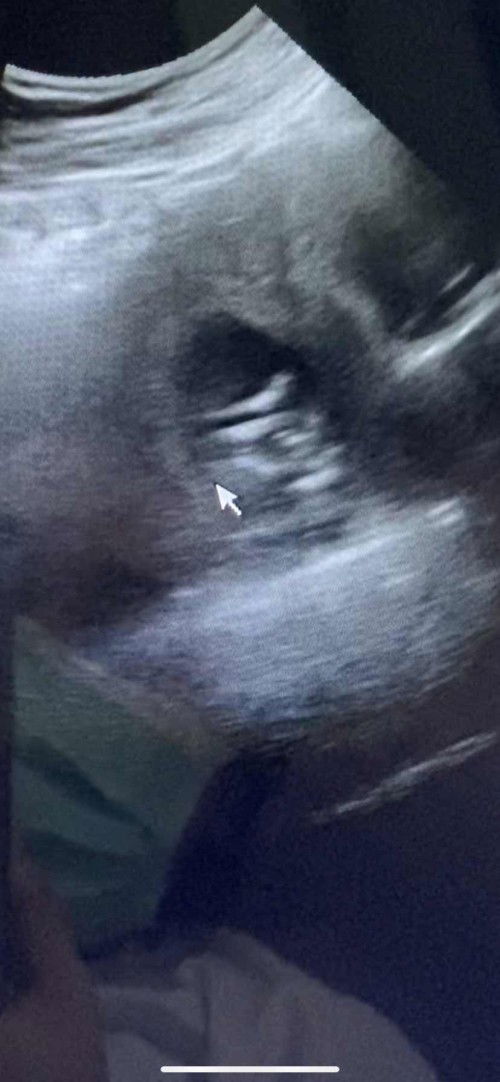

วันนี้ไปพบลุงหมอมา 14w3d ตัวเล็กนอนอ้าซ่าโชว์ลุงหมอ พี่ๆเพื่อนๆว่า ญหรือช ค่ะ 😍❤️

#คุณแม่ๆช่วยแนะนำหน่อยค่ะ #ท้องแรกคะ #หญิงหรือชาย #ลุ้นๆ

ยังเล็กมาก ไม่เห็นเลยค่ะ